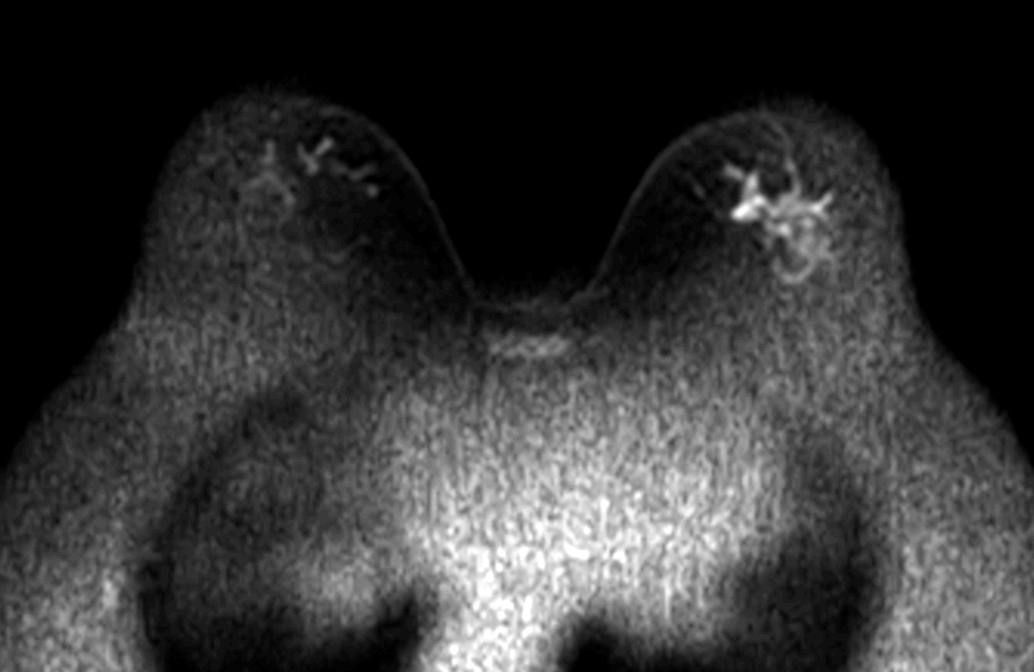

Axial DWI (b800)